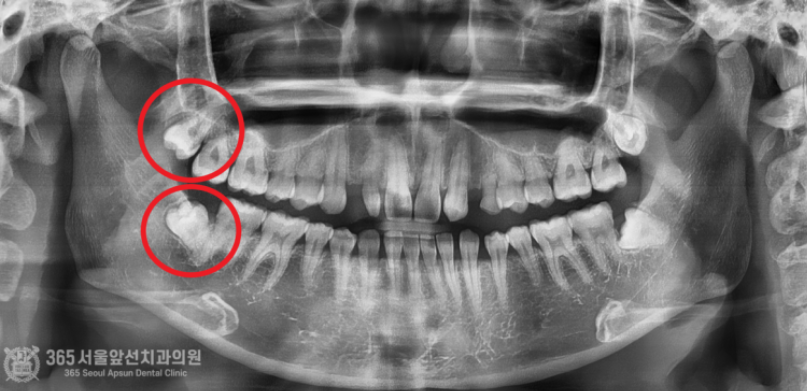

안녕하세요. 주안동치과 365서울앞선치과의원입니다. 하루에도 몇 건씩 사랑니가 불편하셔서 오시는 환자분들을 만나뵙고 있습니다. 환자분들께 치과에 대한 안좋은 기억을 여쭤보면 항상 빠지지않고 나오는 이야기가 바로 사랑니 발치인데요~ 그만큼 많은 환자분들께서 사랑니로 인해 불편감을 호소하고 계시고 발치도 많이 하고 가십니다. 하루에도 몇 건씩 발치를 하다보니 밥먹듯이 하는 진료가 되어버렸네요 ㅎㅎ 촬영일시 : 2024.06.25. 내원 당시 파노라마 엑스레이 사진 입니다. 간단한 사랑니 발치부터 완전 매복 사랑니까지 매일매일 다양한 사랑니 환자분들께서 찾아오십니다. 최근에 오셨던 환자분인신데요. 위와 아래 사랑니가 모두 매복된 형태를 보이고 있습니다. 매일매일 완전매복 사랑니 발치를 시행하고 있기에 매복 사랑니는 대수로운 문제가 아니지만 해당 환자분께서는 조금 특이한 양상이 있어서 포스팅을 하게 되었습니다. 사진 상 빨간색 동그라미 친 아래부분 사랑니의 경우 사랑니의 머리가 설측(혀쪽)으로 향하고 있는데요. 사랑니를 발치할때 기구 접근이 사랑니의 머리쪽으로 이루어져야 하므로, 사랑니 머리가 협측(볼쪽)으로 나와있는 것이 발치에 유리합니다. 즉, 해당 환자분은 사랑니발치 난이도가 꽤 높은 편 에 해당하는 특이한 형태였습니다. 촬영일시 : 2024.06.25. 내원 당시 CT 사진 : 아래쪽 사랑니가 뼈에 거의 묻혀있고 사랑니의 머리가 혀쪽으로 기울어져있는 것이 보입니다. 쉽지 않아보이네요. 촬영일시 : 2024.06.25. 여러 각도에서 CT 분석을 시행합니다. 비록 난이도가 높은 사랑니 발치에 해당했으나, 위아래 사랑니 모두 발치하는 것부터 봉합하는데 걸린 시간까지 총 12분이 걸렸고 환자분께서는 빠르고 정확한 발치에 만족하시며 귀가하셨습니다 ^^ (지혈 거즈를 물고 계셔서 비록 말씀은 못하셨으나 왼쪽 손으로 엄지척 해주셔서 뿌듯했습니다 ㅎㅎ) 촬영일시 : 2024.06.25. 안전하게 발치가 완료된 파노라마 엑스레이 사진입니다. 매일 사랑니 발치와 관련하여 다양한 환자분들을 만나뵙고 있는데요. 환자분들의 고통을 해결해드리고, 치료에 만족하시는 모습을 볼때마다 치과의사로서의 삶에 하루하루 뿌듯함을 느낍니다. 지금까지 365일 열린 가까운 서울대학교 치과병원을 지향하는 365서울앞선치과였습니다. 감사합니다. [ 치료기간: 2024년 6월25일 ] ※ 365서울앞선치과의원의 모든 포스팅은 각 진료과 의료진이 직접 작성합니다. 365서울앞선치과의원 블로그의 임상 케이스 게시물은 환자분께 의학적으로 정확하고 상세한 정보를 드리기 위해 각 진료과 의료진이 직접 작성하며, 모든 증례 사진은 본원 의료진이 직접 시술한 증례를 촬영한 것으로, 의료법 제23조, 제56조에 의거하며 환자분의 동의를 얻어 포스팅에 사용하였습니다. 또한 해당 케이스는 본 환자분의 치료 결과이며, 환자 상태에 따라 치료의 결과는 달라질 수 있습니다. |